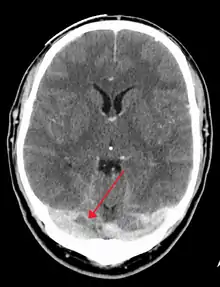

التصوير الطبي

تُوجد العديد من إجراءات التصوير العصبي التي تُساعد في اكتشاف خثار الجيب المخي. قد تكون الوذمة الدماغية والاحتشاء الوريدي ظاهرةً في أي طريقة تصوير، أما للكشف عن الخثرة نفسها، فإنَّ التصوير المقطعي المحوسب (CT) والتصوير بالرنين المغناطيسي (MRI) يُعتبران التقنيات الأكثر شيوعًا لذلك، حيثُ يستخدم كلاهما أنواعًا مختلفة من المواد المظللة لإجراء صورة الوريد، والتي تساعد في إظهار الأوردة حول الدماغ.[6]

يمتلكُ التصوير المقطعي المُحوسب بالمادة المظللة في الطور الوريدي (التصوير الوريدي المقطعي المحوسب) معدلَ اكتشافٍ للحالات يتجاوز التصوير بالرنين المغناطيسي في بعض الأحيان. يجرى الفحص عبر حقن مادةٍ مُشعةٍ معتمة في وريد (غالبًا في الذراع)، ثُم يترك لبعضِ الوقت كي يتسنى لمجرى الدم حمل المادة إلى الأُوردة الدماغية، وعند هذه اللحظة يُجرى التصوير. تبلغ حساسية التصوير حوالي 75-100% (أي يكشف عن 75-100% من الخثرات الموجودة)، كما أنَّ نوعيته حوالي 81-100% (أي يكون إيجابيًا زائفًا في 0-19% من الحالات). في أول أسبوعين، يُمكن ملاحظة علامة دلتا الفارغة (Empty delta sign) والتي قد تختفي في المراحل المُتأخرة.[16]